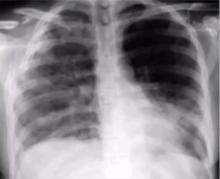

Rib Fractures: Fixation Improves Outcomes [1]

Gonzalo Varela of Salamanca University Hospital, Spain, reviews the evidence for the operative fixation of traumatic rib fractures [3].